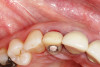

Fig 3. Initial buccal view of tooth No. 7.

Figure 3

Fig 4. Radiograph showing root fracture and apical lesion of the tooth (No. 7).

Figure 4